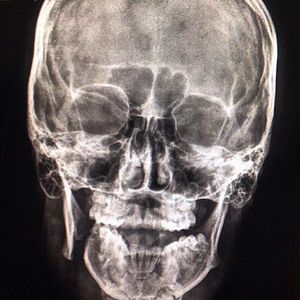

Radiograph of a mandibular fracture

Mandibular fractures are a frequent injury because of the mandible's prominence and relative lack of support.